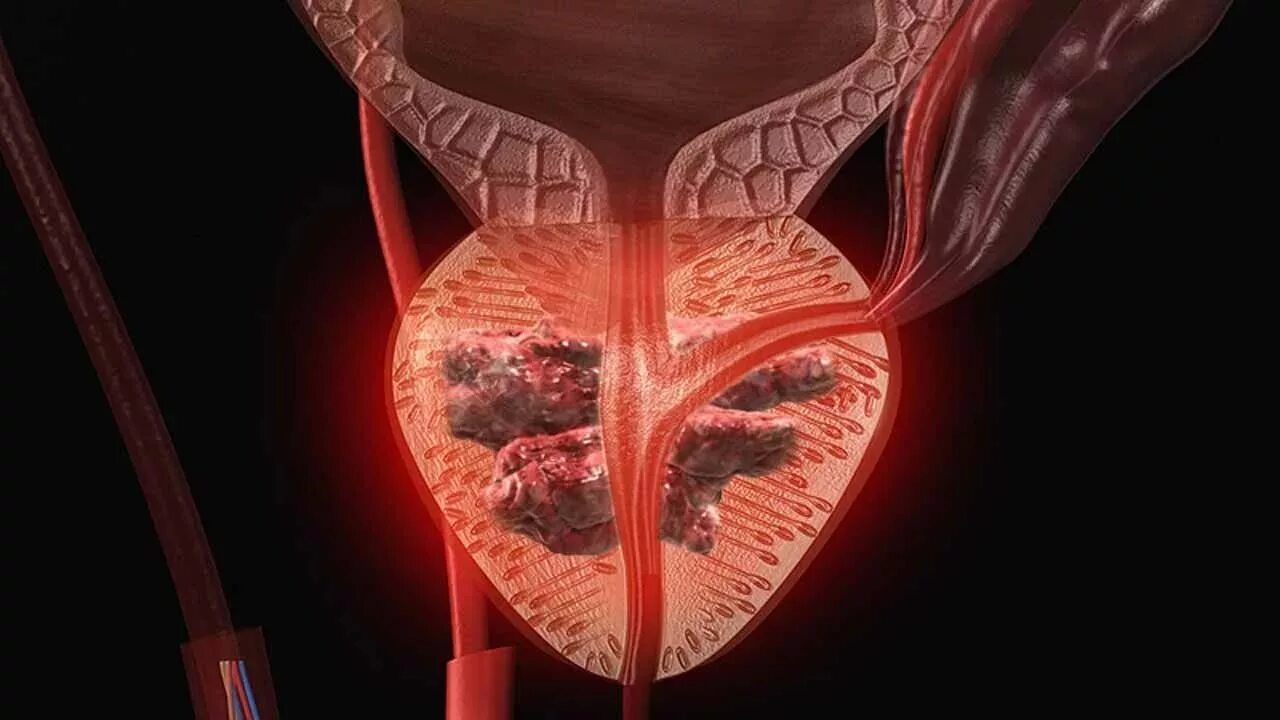

Опухоль аденомы простаты симптомы. Раковые заболевания простаты. Раковая опухоль простаты. Предстательная железа у мужчин онкология Злокачественная опухоль простаты. Злокачественное новообразование предстательной железы. Злокачественные новообразования простаты

Злокачественная опухоль простаты. Злокачественное новообразование предстательной железы. Злокачественные новообразования простаты Карцинома предстательной железы. Злокачественное новообразование предстательной железы. Cancer предстательной железы. Аденома предстательной железы – это опухоль

Карцинома предстательной железы. Злокачественное новообразование предстательной железы. Cancer предстательной железы. Аденома предстательной железы – это опухоль Предстательная железа, Prostata. Аденома предстательной железы. Карцинома предстательной железы. Злокачественное новообразование предстательной железы

Предстательная железа, Prostata. Аденома предстательной железы. Карцинома предстательной железы. Злокачественное новообразование предстательной железы Cancer предстательной железы. Аденокарцинома предстательной железы. Онкология предстательной железы

Cancer предстательной железы. Аденокарцинома предстательной железы. Онкология предстательной железы Опухоль предстательной железы у мужчин. Злокачественное новообразование предстательной железы. Эктопия предстательной железы. Карцинома предстательной железы

Опухоль предстательной железы у мужчин. Злокачественное новообразование предстательной железы. Эктопия предстательной железы. Карцинома предстательной железы